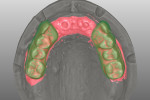

The generated standard tessellation language (STL) files were overlapped and imported into a CAD software (exocad® DentalCAD, exocad GmbH, exocad.com) coupled with a CAM milling unit (Tizian Cut eco plus; Schütz Dental Group, schuetz-dental.de) (Figure 7). Prosthesis prototypes were milled from prefabricated polymethyl methacrylate (PMMA) blocks (ZCAD™ Temp-Fix 98, Harvest Dental Products, harvestdental.com) (Figure 8).

At the next clinical visit, try-in of the PMMA prostheses was performed, followed by confirmation of esthetics and phonetics after minor modifications. The adjusted PMMA prototypes were scanned again and the CAD files were used to mill three maxillary FDPs (Figure 9) and three mandibular FDPs. Minor facial cutback was incorporated on the maxillary FDPs and the anterior mandibular FDP for porcelain veneering to enhance the esthetics. The definitive prostheses were milled (Tizian Cut eco plus) from zirconia monoblocks (Katana™ Zirconia HT, Kuraray Noritake Dental Inc, kuraraynoritake.com) and tried in (Figure 10). Feldspathic porcelain was used to veneer the facial aspect of the FDPs. Mutually protected occlusion with anterior guidance was the prescribed occlusal scheme.